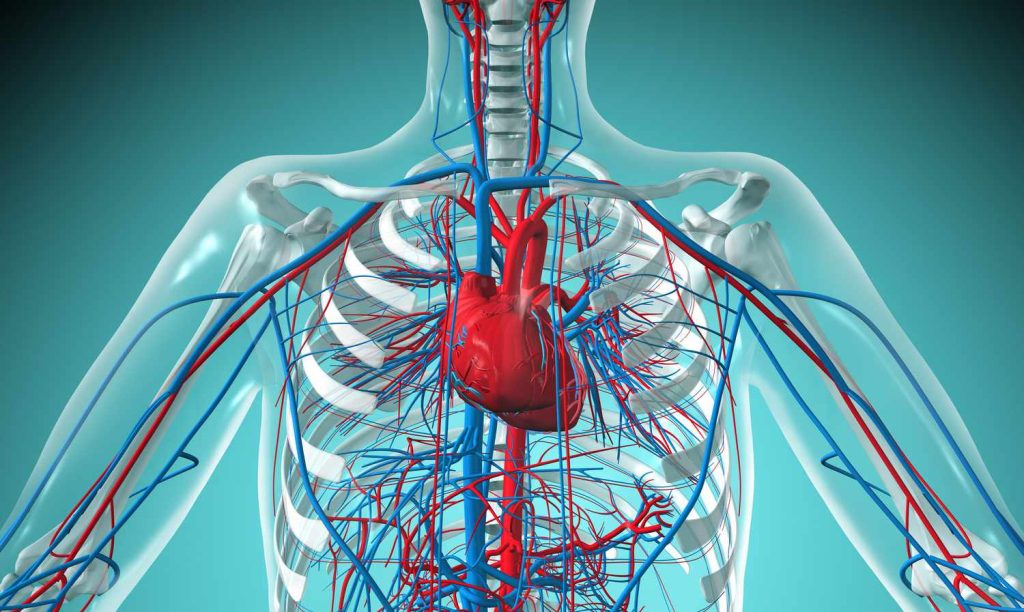

وریدهای ریوی جزء جالبی از سیستم گردش خون هستند که مسئول حمل خون اکسیژن دار از ریه ها به قلب هستند. این رگ های خونی نقش حیاتی در حفظ سلامت و تندرستی کلی ما دارند. در حالی که آنها ممکن است ساختارهای ساده ای به نظر برسند، بسیاری از حقایق جالب در مورد وریدهای ریوی وجود دارد که بسیاری از مردم از آنها بی اطلاع هستند. در این مقاله، ۱۲ حقیقت جذاب در مورد رگ های ریوی را بررسی خواهیم کرد که شما را از پیچیدگی و اهمیت این رگ های خونی کوچک و در عین حال قابل توجه شگفت زده می کند . از نقش منحصر به فرد آنها در اکسیژن رسانی گرفته تا ارتباط آنها با شرایط مختلف پزشکی، ما به دنیای پیچیده وریدهای ریوی خواهیم پرداخت و درک عمیق تری از عملکرد آنها در بدن انسان به دست خواهیم آورد.

وریدهای ریوی نقش مهمی در سیستم گردش خون دارند و مسئول حمل خون غنی از اکسیژن از ریه ها به قلب هستند. این خون اکسیژن دار سپس به بقیه بدن پمپ می شود و از تامین اکسیژن حیاتی بافت ها و اندام ها اطمینان حاصل می کند.

برخلاف سایر وریدهای بدن، وریدهای ریوی منحصر به فرد هستند زیرا خون اکسیژن دار را حمل می کنند. این به این دلیل است که آنها خونی را که در ریه ها اکسیژن رسانی شده است را برای توزیع به بقیه بدن منتقل می کنند.

در بدن انسان ، چهار ورید ریوی وجود دارد – دو رگ از ریه چپ و دو رگ ریه از ریه راست. این سیاهرگ ها قبل از ورود به دهلیز چپ قلب با هم ادغام می شوند.

سیاهرگ های ریوی به صورت رگ های خونی ریز به نام مویرگ ها در ریه ها شروع می شوند. این مویرگ ها شبکه های متراکمی را در بافت ریه تشکیل می دهند و به تدریج با هم ادغام می شوند و در حالی که به سمت قلب حرکت می کنند وریدهای بزرگتری را تشکیل می دهند.

ساختار وریدهای ریوی متمایز است، زیرا دارای یک دیواره بیرونی ضخیم، یک لایه میانی نسبتا نازک و یک پوشش داخلی صاف هستند. این ساختار منحصر به فرد، انتقال کارآمد خون اکسیژن دار را به قلب تضمین می کند.